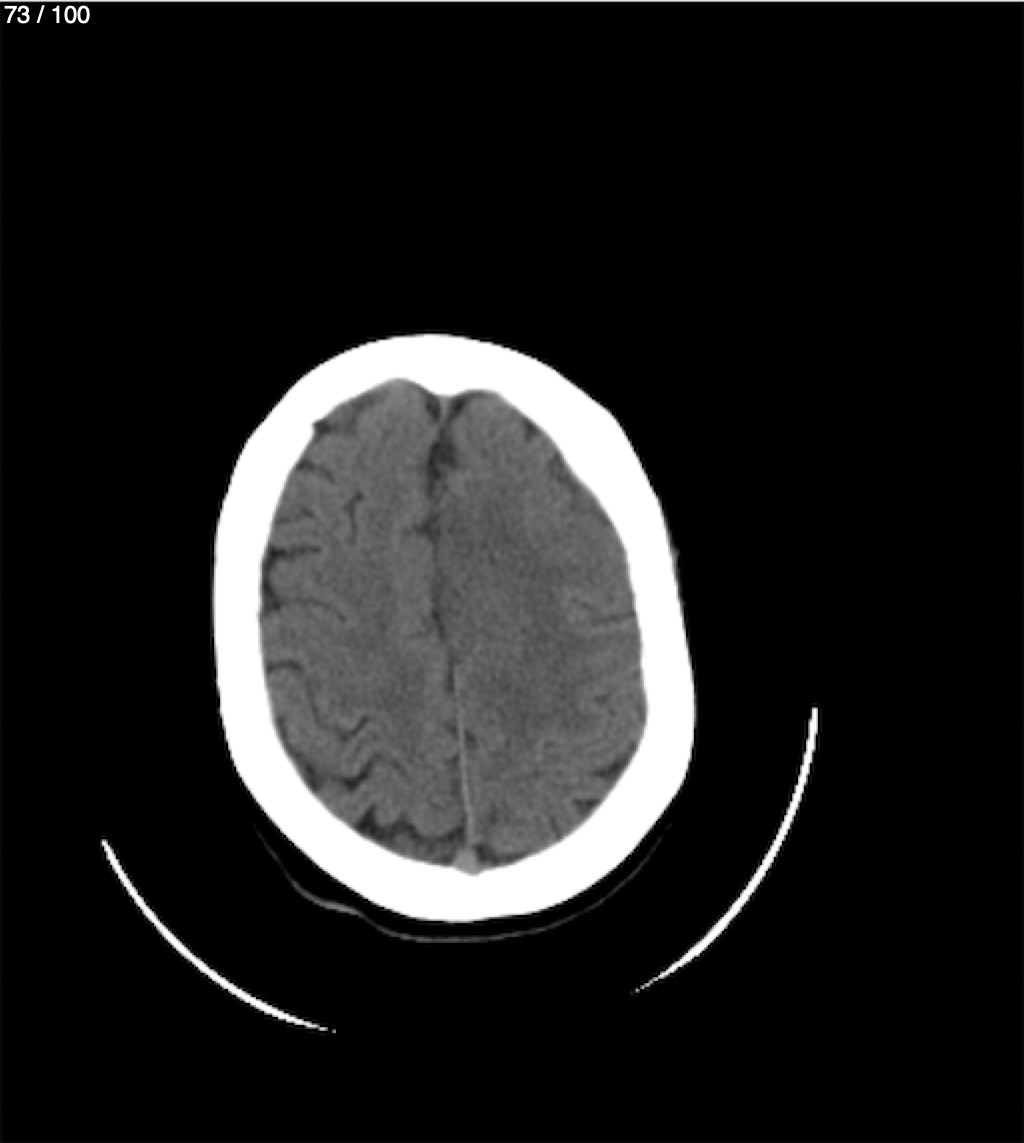

Valentin Perez Gomez 69A - T.C Craneo